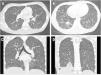

We describe the case of a male adolescent aged 17 years admitted for severe acute respiratory failure with hypoxaemia. During the hospital stay, numerous diagnostic tests were performed, and the findings of the computed tomography scan of the lungs proved key to the diagnosis, with visualization ground glass micronodules with tree-in-bud opacities and a diffuse distribution1 (Fig. 1).

Computed tomography images obtained during the hospital stay. Axial (A and B) and coronal (C and D) images showed small micronodular opacities in a diffuse tree-in-bud pattern, without involvement of the subpleural region. Images B and D evince the presence of consolidations in the right lower lobe.